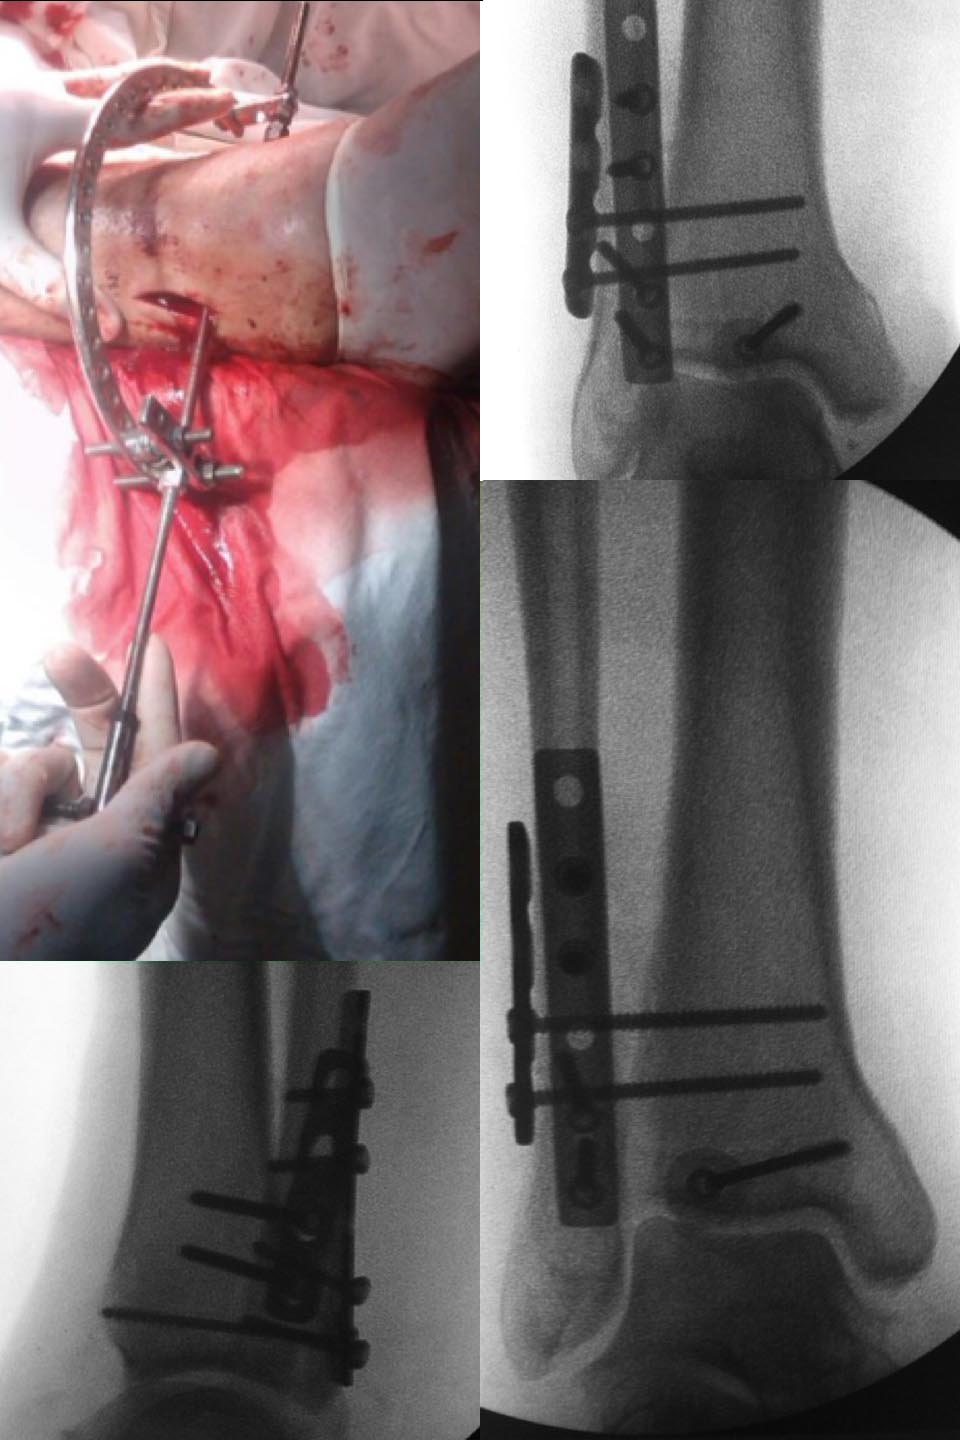

4. Для правильного позиционирования м/б кости я как то использовал импровизированый аппаратик из деталей АИ.

Во вложении похожий случай. Первый синтез я сделал через 10 дней после травмы, а вторая операция через 2 месяца после первой.

Здравствуйте, коллега! Методички нет. На самом деле, ничего оригинального. С инструментами было туговато и импровизация мысли привела к созданию такого устройства. С таким же механизмом можно и из других деталей собрать.

IMG_3588.JPG